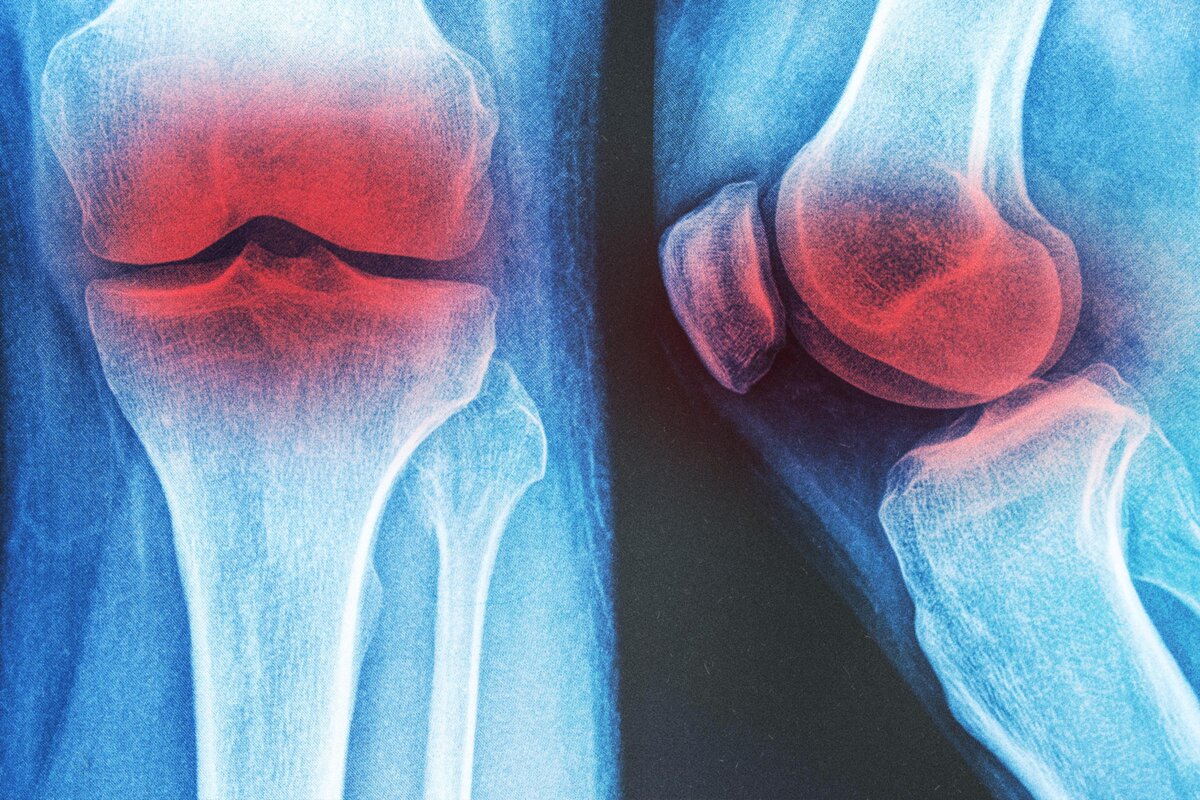

Physiotherapist Alex Lee had a 64-year-old patient with knee arthritis. She experienced difficulty walking for more than 10 minutes at a time because of pain. Her stiff knee joints and weak leg muscles made her afraid of falling.

Approximately 10 percent of men and 13 percent of women older than 60 have knee arthritis, a condition associated with pain and disability.